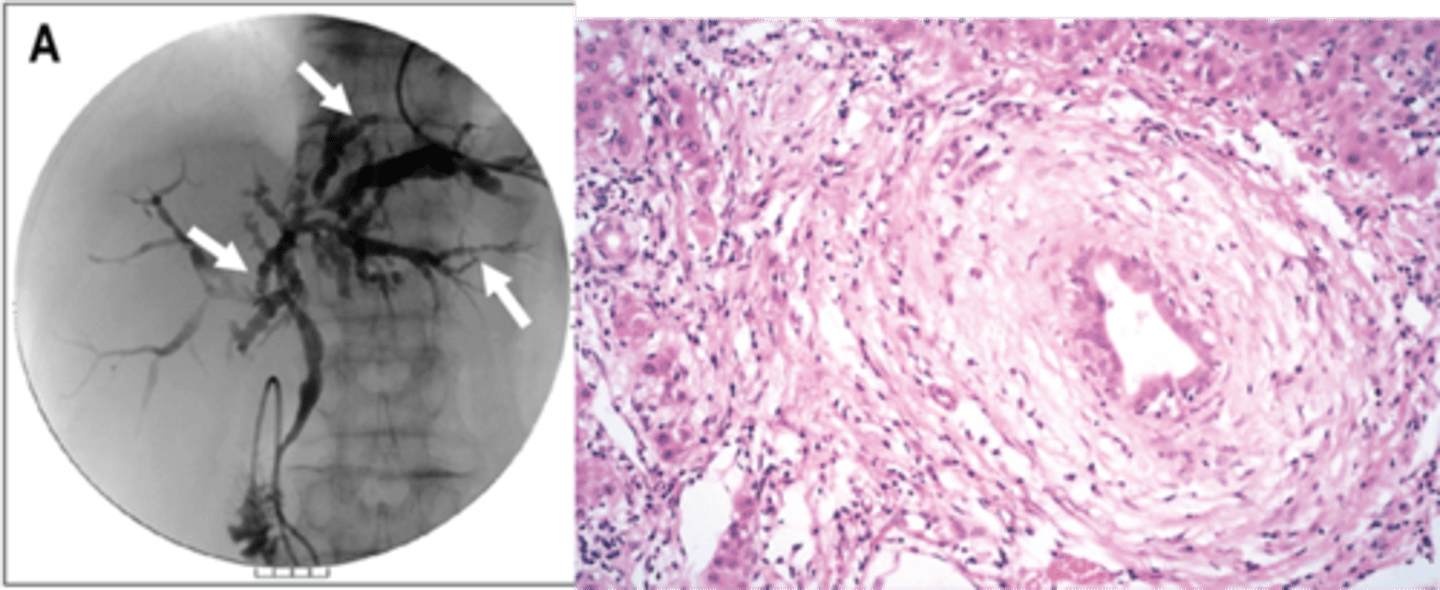

Primary Sclerosing Cholangitis (PSC)

Define Condition:

Autoimmune condition causing inflammation and obliterative fibrosis of intrahepatic and extrahepatic bile ducts

-Hx:

> More in MALES

> Strong a/w Ulcerative Colitis

-Sx/PE:

> Fatigue

> Pruritus

> Jaundice

-Dx:

> (+) MPO-ANCA/p-ANCA (80%)

> Gross:

>> End-Stage = Cirrhosis

> Biopsy:

>> Large bile ducts with acute & chronic inflammation

>> Small ducts have little inflammation but show circumferential "onion skin" fibrosis and atrophic duct lumen --> duct obliteration --> fibrosis/cholestasis ==> Cirrhosis

> Cholangiogram: confirms Dx

>> ERCP & MRCP

>> Shows alternating strictures and dilation "beading" of intra- and extrahepatic bile ducts

-Prog:

> Chronic Pancreatitis/Cholecystitis d/t extrahepatic bile duct involvement

> Median Survival = 10-12 yrs

> Increased risk of Cholangiocarcinoma and HCC